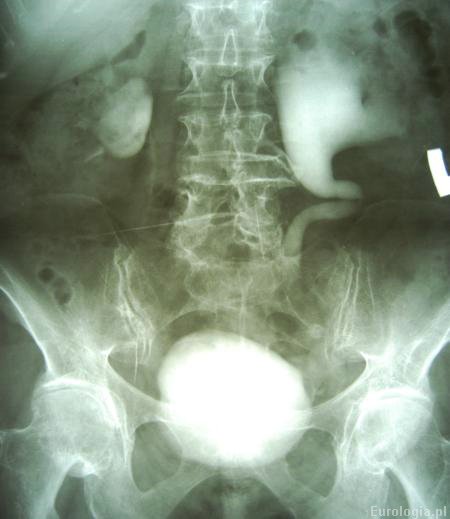

Fot. Wodonercze lewostronne - urografia